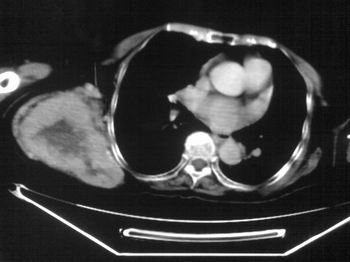

以下是引用zhangxu5888在2007-9-11 16:25:00的发言:[br]有侧肩胛骨溶骨性破坏且见软组织成分,增强软组织强化明显,中央见低密度坏死区!根据病史10年,考虑良性肿瘤恶性变!性质待定!

以下是引用老爱克斯新网客在2007-9-11 18:22:00的发言:[br]应该是良性肿瘤恶变,但因晚期破坏严重不能见到原来肿瘤征象无法判断,